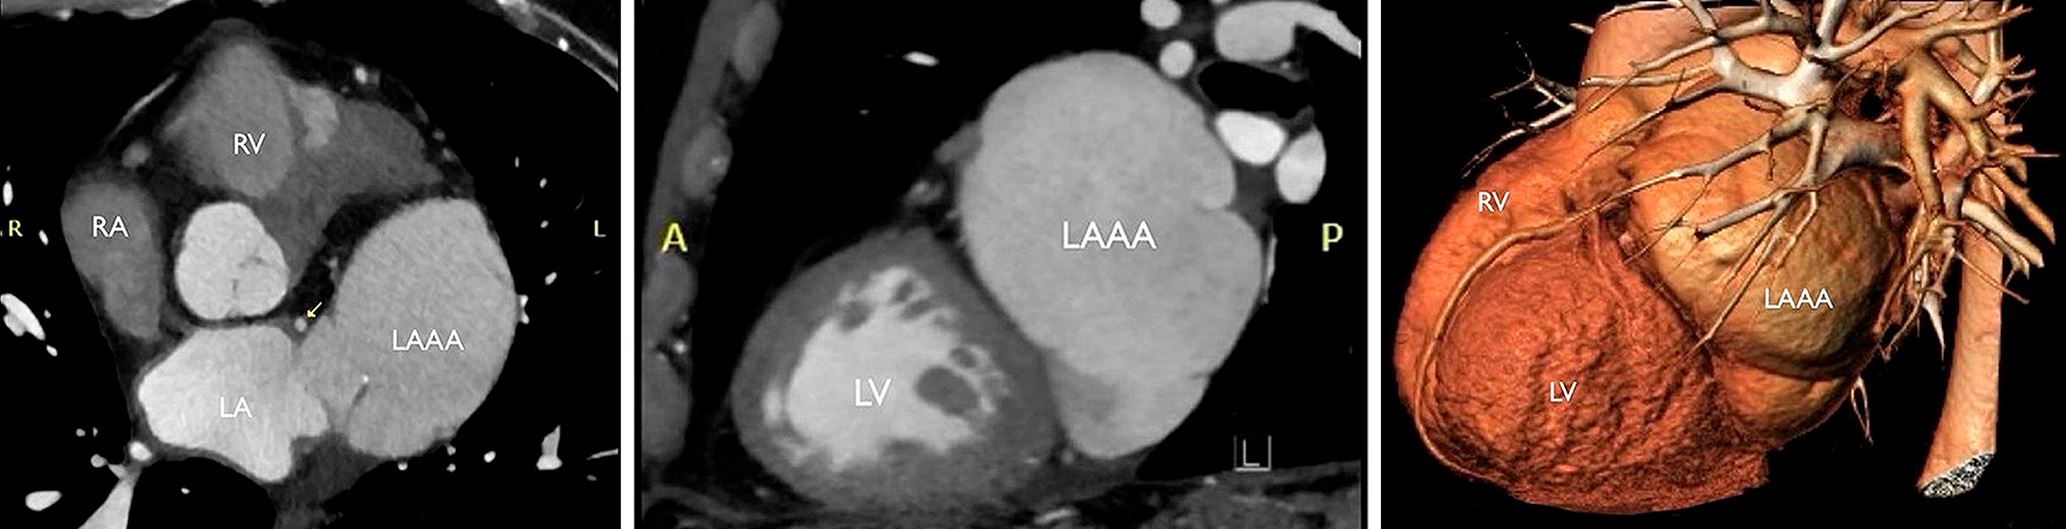

Herz-CT und 3D-Rekonstruktion mit den Herzkammern (RV, LV), den Vorhöfen (RA, LA) und dem Aneurysma des linken Vorhofohrs (LAAA).